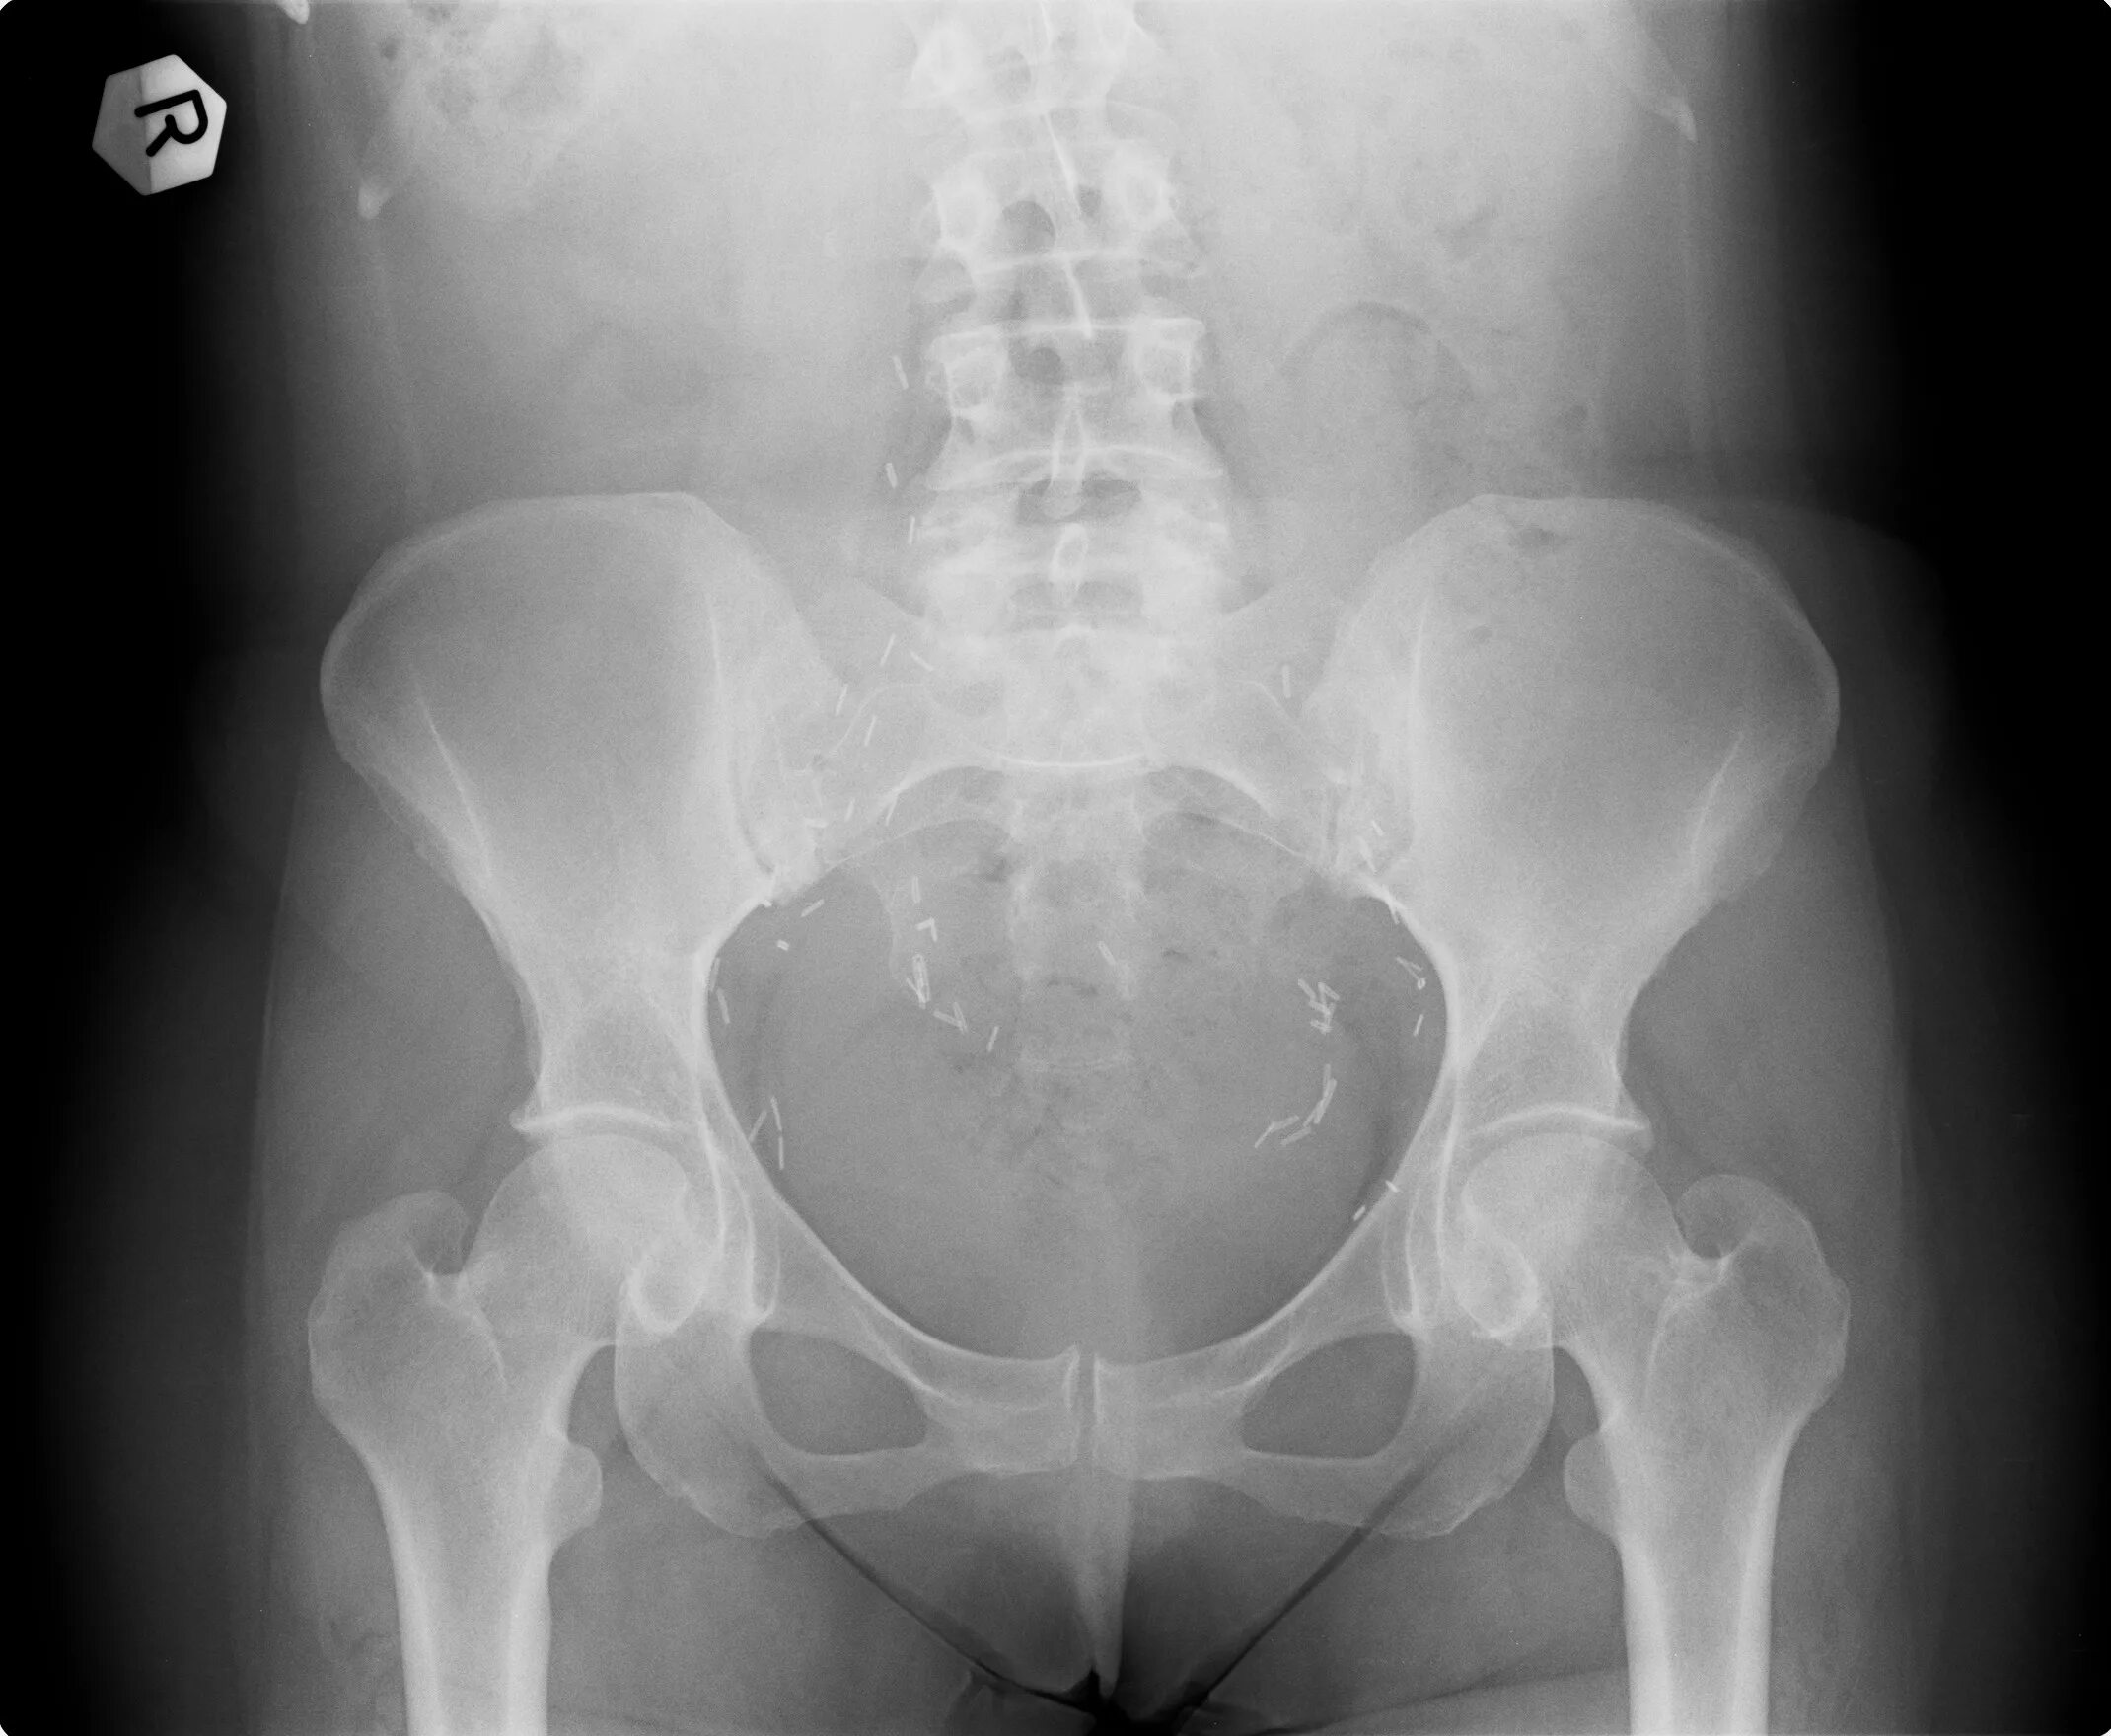

Как прочитать снимок